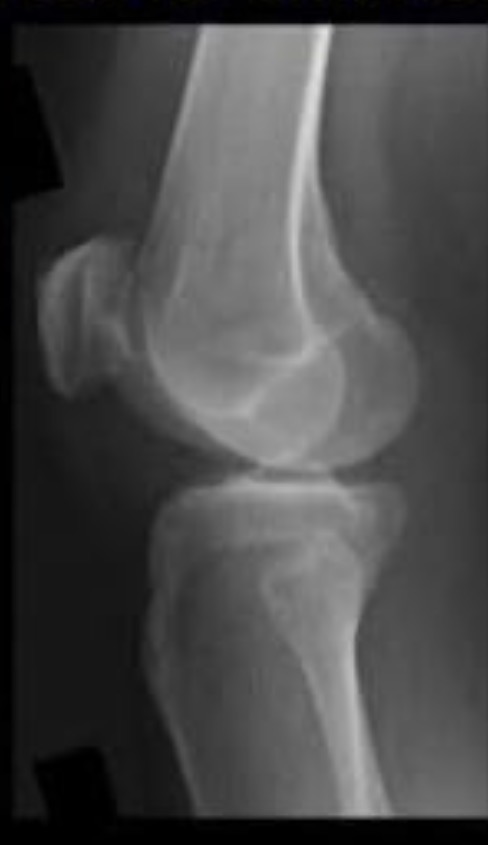

Name the projection.

Should it be repeated, if so why?

AP Knee

No

Label the image

A) Femur

B) Patella

C) Lateral femoral epicondyle

D) Intercondylar fossa

E) Intercondylar eminence

F) Femorotibial joint

G) Fibula

H) Tibia

I) Tibial condylar margin

J) Medial femoral epicondyle